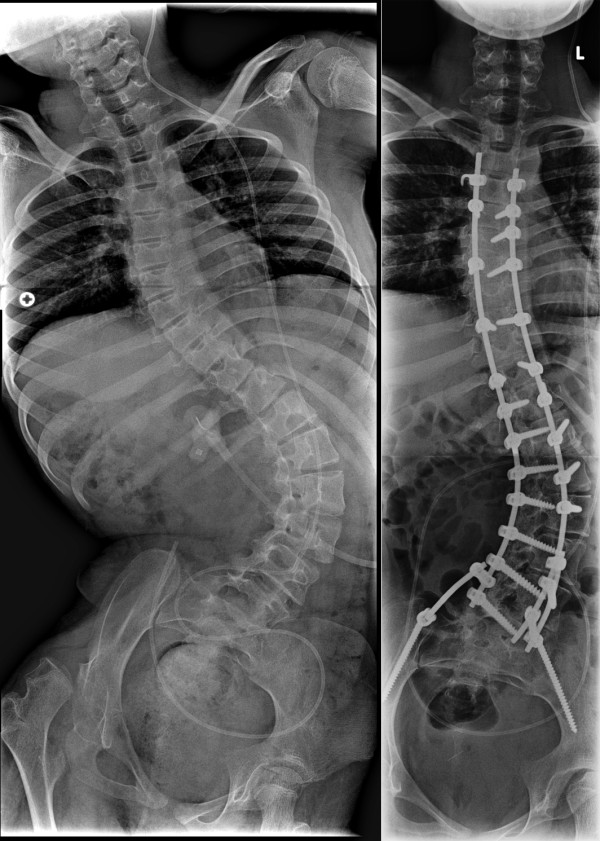

Οι χειρουργικές επεμβάσεις για τις νευρομυϊκές σκολιώσεις είναι περίπλοκες, εξαιτίας των βιολογικών αποτελεσμάτων λόγω της ασθένειας που δημιούργησε την σκολίωση, όπως η αναπνευστική δυσλειτουργία, η αδυναμία των οστών και η φτωχή θρέψη των ασθενών. Ανάλογα με το είδος της πάθησης, εφαρμόζεται πρόσθια ή οπίσθια σπονδυλοδεσία, που κάποιες φορές περιλαμβάνει μέχρι και την λεκάνη, όταν υπάρχει έντονη κλίση της από την μία μεριά. Η επέκταση της σπονδυλοδεσίας στο ιερό οστό γίνεται για να επιτευχθεί καλύτερη σταθεροποίηση, καθώς ο στόχος στις νευρομυϊκές σκολιώσεις δεν είναι τόσο η διόρθωση της γωνίας ή του αισθητικού αποτελέσματος, όσο η καρδιοαναπνευστική βελτίωση και η καλή λειτουργικότητα του ασθενούς.